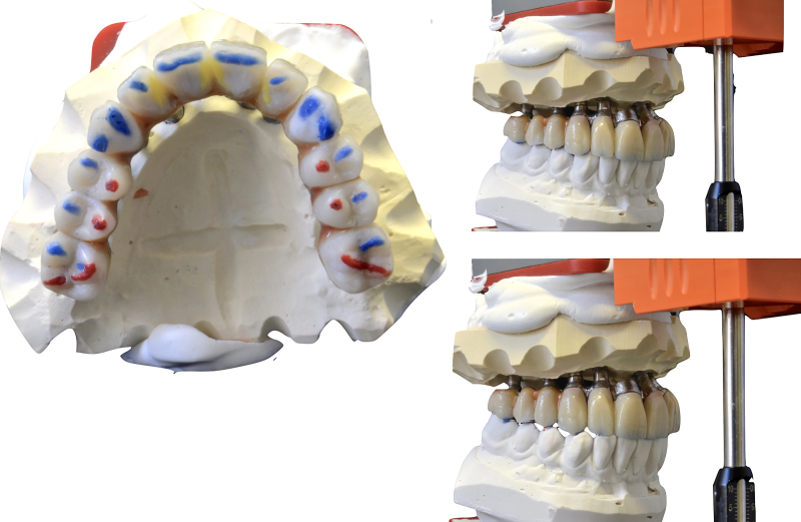

L’ADSD e il Cad per il paziente sono stati quindi eseguiti a partire dalle foto e dai modelli virtuali che definivano il nuovo piano occlusale. Poiché gli impianti superiori non potevano essere caricati immediatamente, una mesostruttura avvitata di prova in alluminio è stata fresata al Cam per la sola mandibola, insieme a una ceratura preliminare, con denti singolarmente staccabili, per la rifinitura sequenziale (Fig. 17). I modelli con la ceratura preliminare fresata sono quindi stati trasferiti nuovamente sull’articolatore SL, ed essa è ulteriormente perfezionata dall’odontotecnico esperto, che ha modellato accuratamente le superfici funzionali secondo il modello di occlusione sequenziale ispirato a quello proposto dal Prof. Dr. R. Slavicek, con cere di diverso colore a evidenziare i rapporti di centrica, le funzioni di mediotrusiva e protrusiva, e le protezioni di retrusiva (Fig. 18). Sono stati controllati tutti gli aspetti dell’occlusione, le guide funzionali sequenziali e l’uniformità delle disclusioni (Fig. 19).